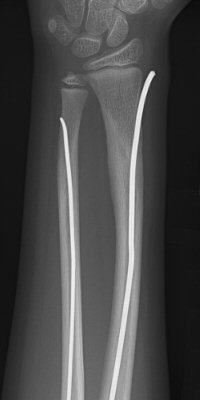

Distala diafysära radius- och ulnafrakturer, opererade med TEN-spikar, sista bilderna läkt efter 7 månader. Alla bilderna är från samma patient.